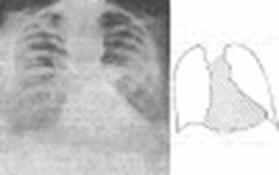

Характерные изменения мы можем увидеть при рентгенографии грудной клетки. Обращает внимание: горизонтальное положение ребер, увеличение межреберных промежутков, высокое стояние диафрагмы, ослабление сосудистого рисунка, уменьшение объема легких, поперечник тени сердца расширен в обе стороны на 25-55% больше нормы. В боковой проекции определяется усиленный кифоз грудного отдела позвоночника.

Типичная рентгенограмма грудной клетки у лица с ожирением (мужчина 36 лет, фактическая масса тела 106 кг, рост 169 см).